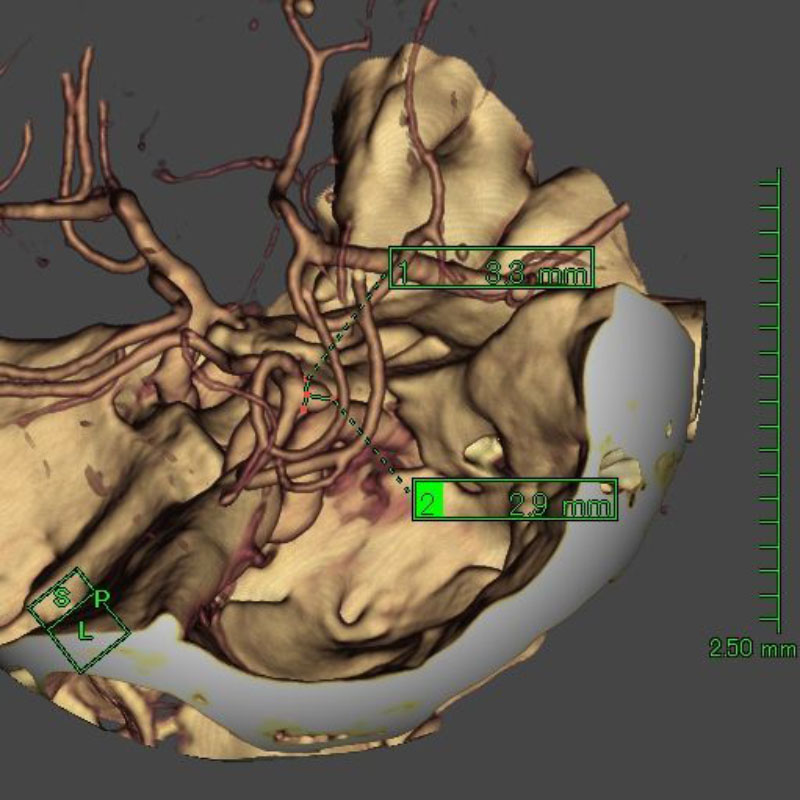

※ 画像をクリックすると拡大表示します。症例No.をクリックすると詳細ページを表示します。

手術前

クリップ前

クリップ後

手術後